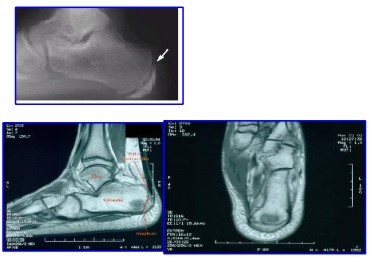

Sever

Apofisite do calcâneo

Necrose avascular da placa epifisária da apófise do calcâneo

Kohler

Osteonecrose do navicular por stress mecânico ou alteração da vascularização

Achatamento, esclerose e fragmentação do navicular